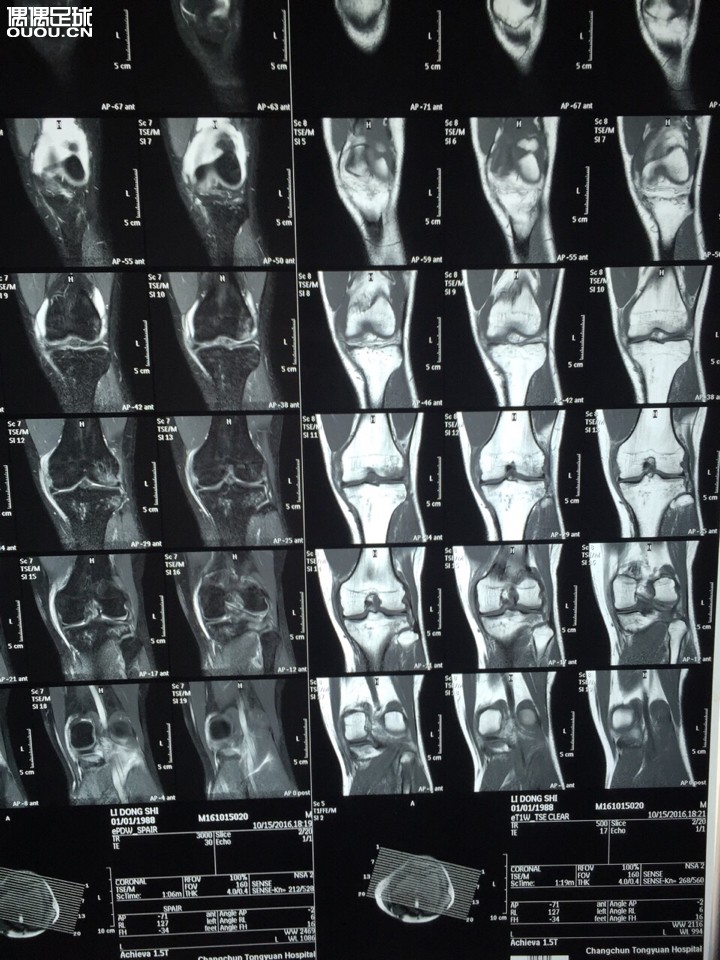

去年右膝十字韧带让人撞断了 刚恢复没踢几场左膝又自己扭断了